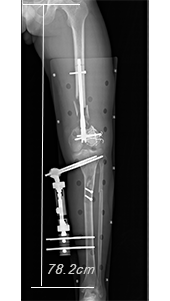

Slot images are acquired using a narrow perpendicular X-ray beam tracking past the patient, producing a long image with almost no geometric distortion or magnification and very accurate measurements.

In Slot Advance, due to the perpendicular nature of the X-ray beam, there is practically no geometric distortion or elongation of the acquired image.

As such, the resultant Slot Advance images are very accurate in their anatomic representation.

Experiences with Slot Radiography for Limb Lengthening Surgery

The introduction of Slot Radiography resolves many existing problems in long limb imaging and in particular with regards to limb lengthening. Read more......